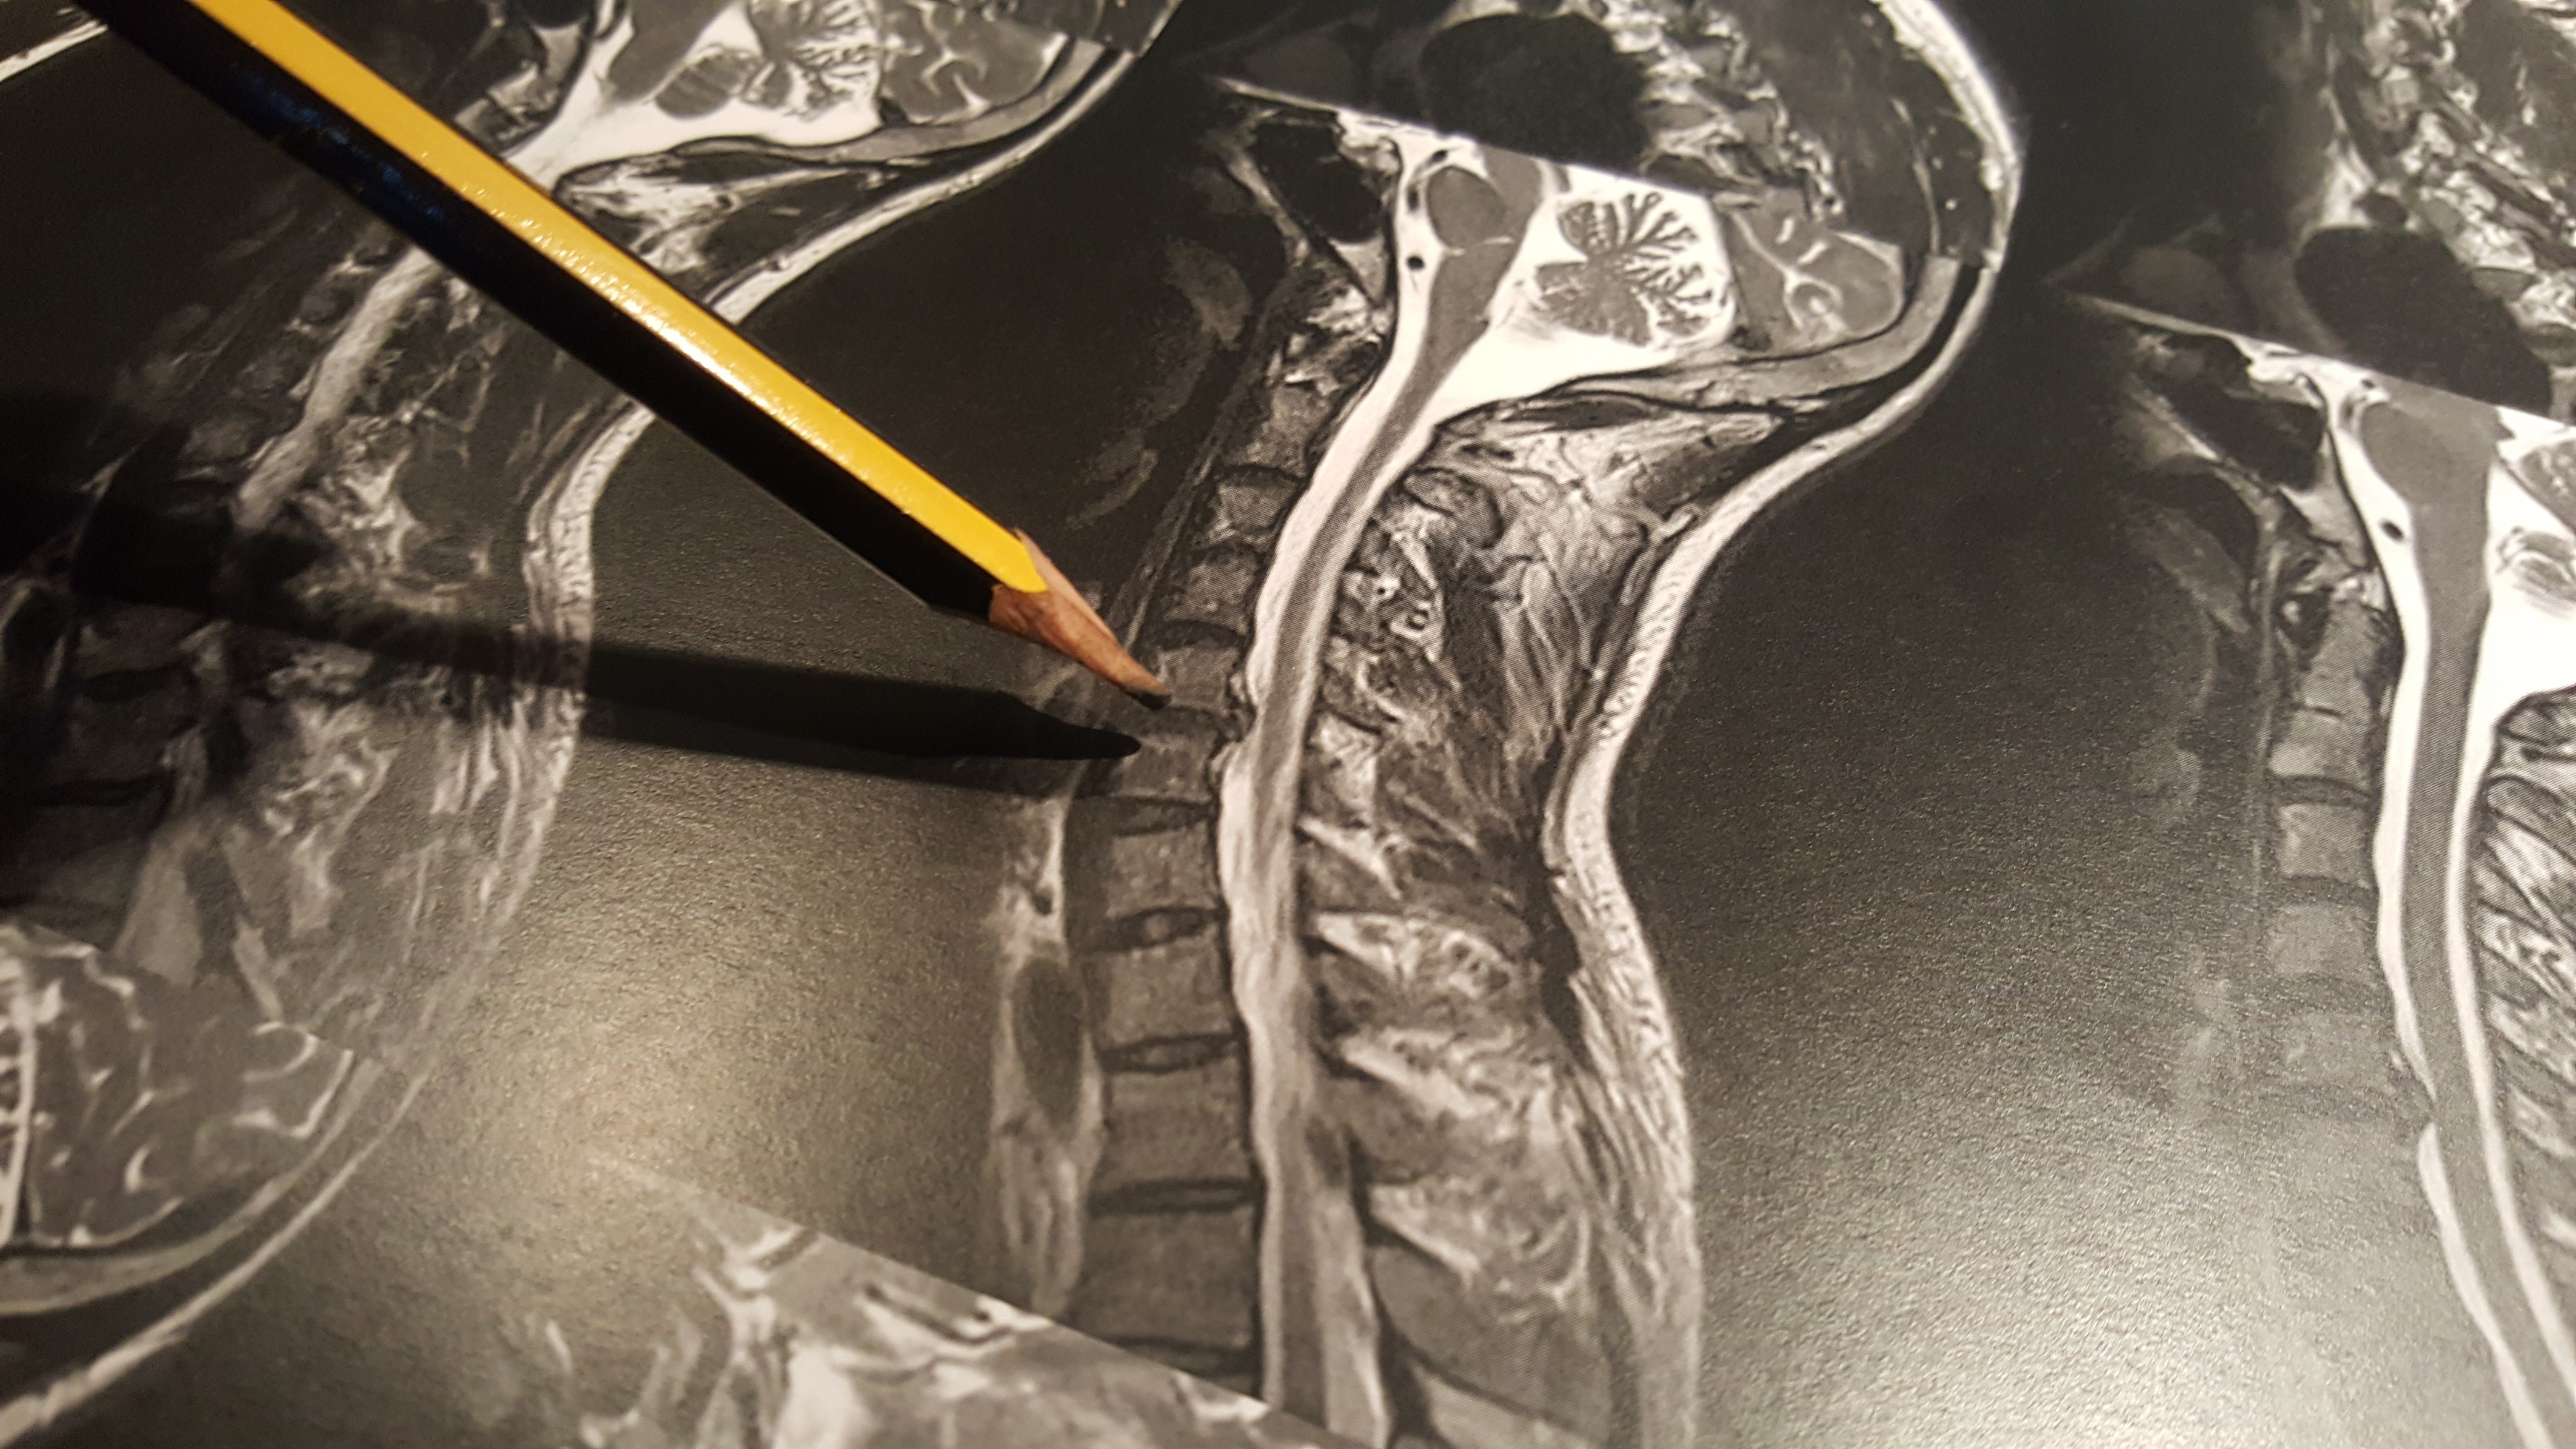

The symptoms of my herniated disc started with numbness in my right thumb, it wasn't until a couple of weeks later that I saw my GP about it, he immediately diagnosed a herniated C5/C6 disc (at the top of teh spine). The nerve that is being comressed by that particular herniated disc is the one that causes the numbness is the thumb apparantely. I've had an MRI to confirm it as you can see and he's referred me to a surgeon.

It too was diagnosed finally with an MRI. My GP hadn't managed to fix what we thought might be a different issue, and she called the hospital with the MRI scanner on a thursday aftenoon and I was seen on the monday, left with a CD containing the images and a program to view them, and my GP had a fax with the analysis two days later.

Depending where and how a disc has herniated can dictate surgical treatment options should that be the path decided on. The most common surgical intervention for a cervical disc herniation is going in from the front (actually to the side as well even though it's called an, 'anterior' approach, removing the disc and then fusing the two vertebra together by use of a bone block or an implantable spacer with bone material in it. Using such a spacer regains the height of the disc space thus opening the canal where the nerve root is and lessening any chance for further nerve root issues at that level. It is possible to extract the disc from the back, 'posterior approach' though this is made more difficult due to the vertebral artery. Lack of working space can make jacking the disc up and placing an implant to maintain height next to impossible which means doing this fails to address future potential root issues and allows possible re-herniation as the disc remains. A fusion can be done via screws and rods or plates from the back but would not be usual for this indication. In the past 15 years disc replacement surgery has gone in and out of fashion. Implants that mimic some of the motion of a normal disc have been used, sometimes with great success. In the cervical area the results for a plain anterior intervertebral fusion are so good in the hands of experienced surgeons that the use of disc replacement and some of the issues is not widespread. The nice theory of disc replacement is that maintaining motion in the segment reduces the stresses that can be place on the segment levels above as well as maintaining disc space height. The spine works like a mast on a ship with stresses reduced as movement travels up the spine. Fuse a level and it makes the level above work more than is normal thus increasing potential issues. However, there have been issues with disc replacement and some conjecture whether there is the amount of movement reported.